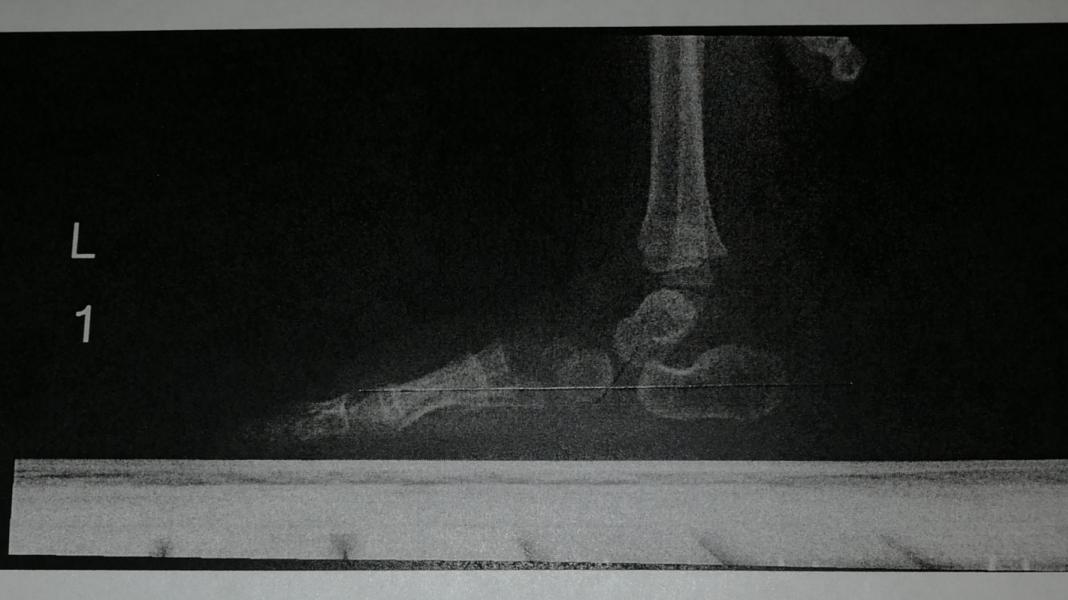

Ахеренная мать. У ребёнка сломаны обе ноги. Подумаете вы, увидев нас на улице или просто эти фотографии. Но это не так.

Кто-нибудь слышал про Косой таран? Вот и я нет. Это врождённая патология стоп.

Я расскажу здесь нашу историю, так как я искала и ничего не нашла и может кому-то она поможет.

Мамы которые столкнутся с такой-же проблемой вы можете написать мне, для моральной поддержки и подробной информации, моя страница в инстаграм daria_kova174

ЧАСТЬ 1.

Нам потребовалось 3 ортопеда, чтобы ...